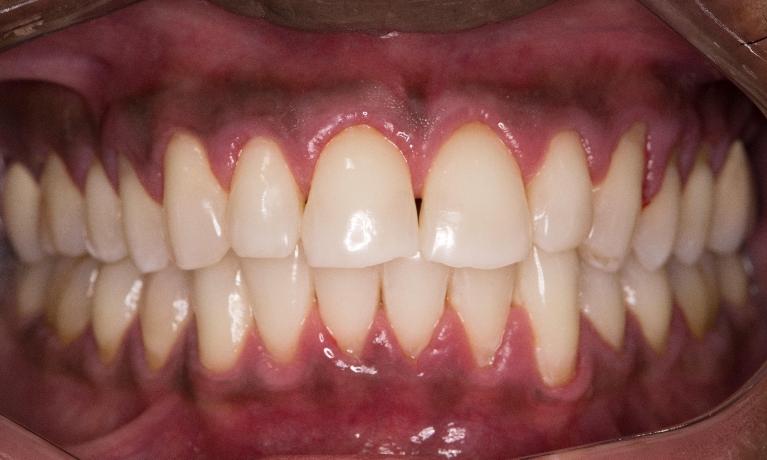

Upper & Lower, All on 4 fixed implant teeth with finals. Patient went home with temp fixed teeth the same day.